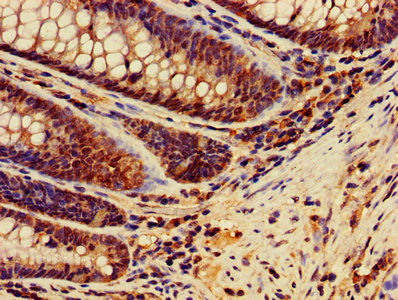

IHC image of CSB-PA16889A0Rb diluted at 1:400 and staining in paraffin-embedded human colon cancer performed on a Leica BondTM system. After dewaxing and hydration, antigen retrieval was mediated by high pressure in a citrate buffer (pH 6.0). Section was blocked with 10% normal goat serum 30min at RT. Then primary antibody (1% BSA) was incubated at 4°C overnight. The primary is detected by a biotinylated secondary antibody and visualized using an HRP conjugated SP system.